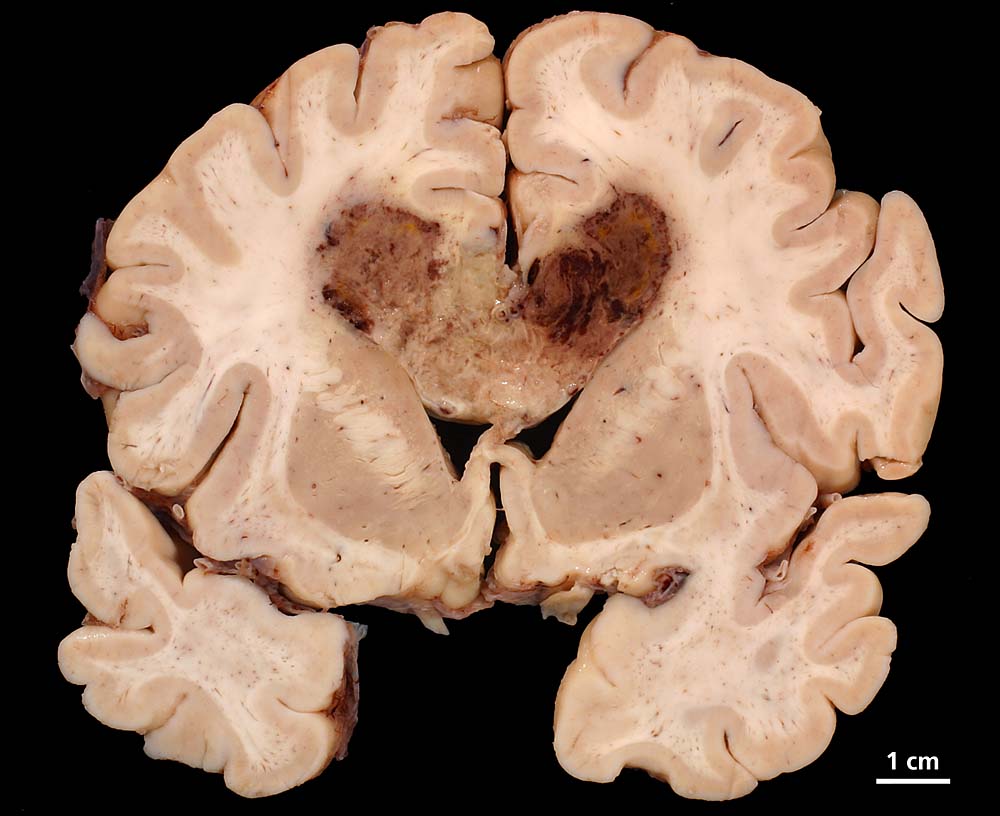

PathoPic – image database / PathoPic ID 8568 - Glioblastoma multiforme

Glioblastoma multiforme

Bräunlich verfärbter "Schmetterlingsförmiger" Erweichungsherd im Bereich des corpus callosum.

Vor einem halben Jahr Wesensveränderung, Aphasie, psychomotorische Verlangsamung, Harninkontinenz. Computertomographisch Verdacht auf Glioblastoma multiforme im Bereich des Truncus corporis callosi. Einen Monat später zunehmende Verschlechterung des Allgemeinzustandes mit Fieber und Verdacht auf Aspirationspneumonie.